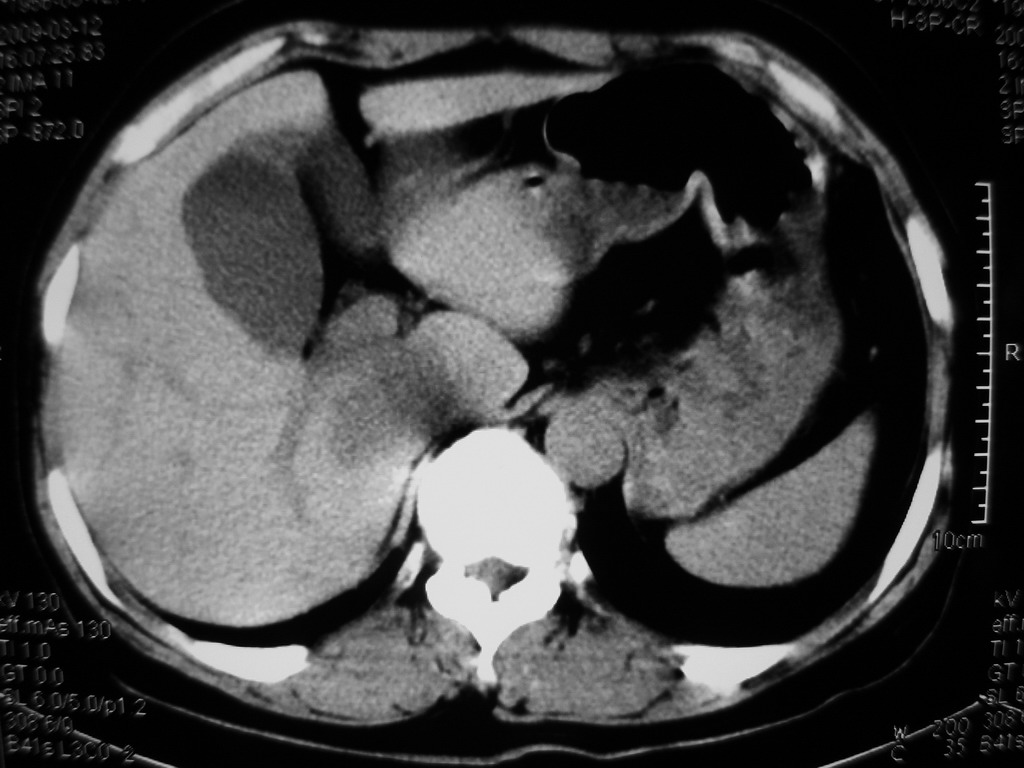

接着往下一贴看,有静脉期和延迟期,在看看和下腔静脉及十二指肠的关系,腔静脉内是不是栓子?

考虑肝右叶与尾叶交界区肝癌(部分外生),侵犯下腔静脉并下腔静脉瘤栓形成。